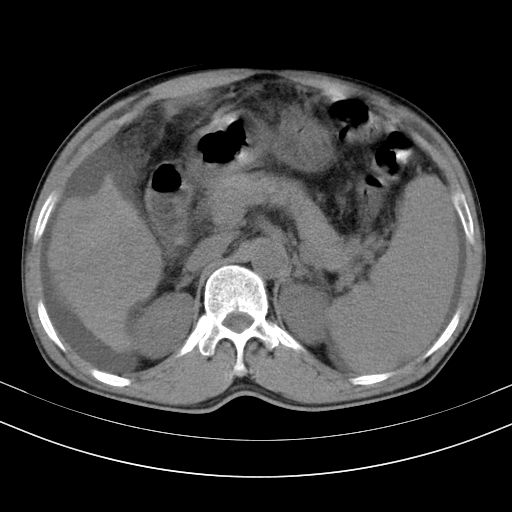

以下是引用随光逐影在2010-2-28 10:23:00的发言:[br]1)考虑肝癌;建议行ct增强扫描检查。2)肝硬化,脾大,腹水。3)慢性胆囊炎。

以下是引用dyqct在2010-2-28 16:44:00的发言:[br][quote]以下是引用随光逐影在2010-2-28 10:23:00的发言:[br]1)考虑肝癌;建议行ct增强扫描检查。2)肝硬化,脾大,腹水。3)慢性胆囊炎。